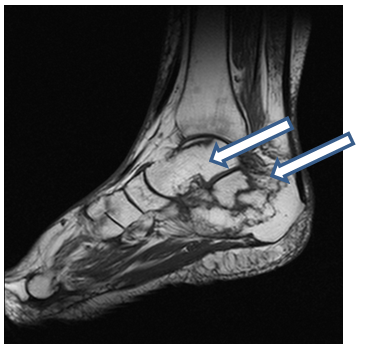

A 66 year old man with seropositive rheumatoid arthritis was diagnosed in 2009. His co-morbidities included emphysema, atrial fibrillation (on warfarin), and chronic haematuria. His medications included etanercept and methotrexate 20mg. This patient had right ankle pain for 5 years, but it was worse in December 2013, so an XR was taken which appeared normal. An ultrasound guided intra-articular steroid injection was performed in February 2014. This did not alleviate the pain, so a MRI was requested. It which showed non-displaced insufficiency fractures of the cuboid and talar neck, which appeared to be healing. There was also pes planus with lateral hind foot talocalcaneal impingement. He was reviewed by orthopaedics and supplied with a Jura-boot with medial arch support (Figure 7-10) (Table 2).

Figure 8 Case 2 MRI sagittal view right ankle. Old healing talar neck fracture.

Figure 10 Case 2 MRI sagital view right ankle. New non-displaced lateral cuboid fracture.